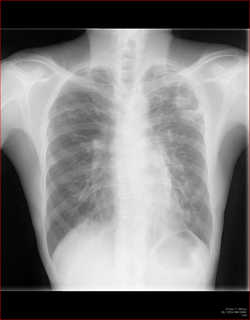

CT全盛の昨今、胸部レントゲン写真の意義は少なく見積もられがちではありますが…。

例えば診療所であったりして、CTはすぐに撮れない、という環境もあるわけです。

胸部レントゲン写真で、ここまでわかるか!というところを何回かに分けて、見て参りましょう。

胸部レントゲンの見方、系統的な見方はポリクリやアドバンスでかなり繰り返していますので改めては書きませんが、大事なポイントをおさらいしておきましょう。